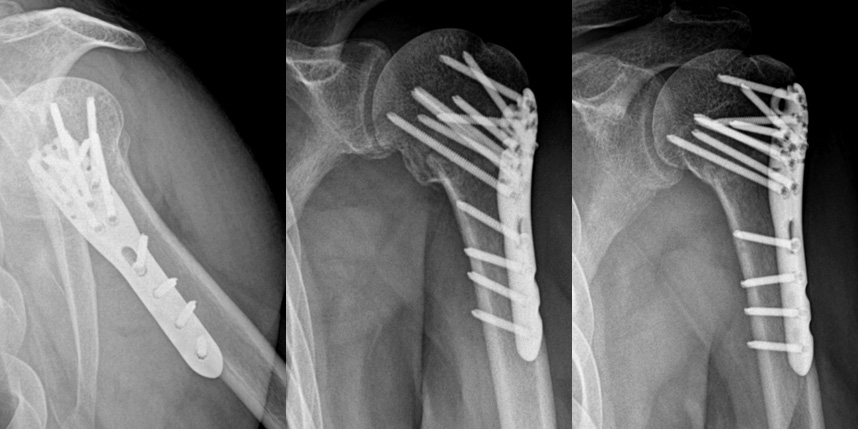

상완골 골절

골절은 정확하게 골절편을 잘 맞추고 고정하는 것이 중요합니다. 특히 관절면을 잘 맞추는 것이 중요합니다.

감탄정형외과는 정확한 초기 진단을 통해 골절 발생일로부터 최대한 빨리 원래의 뼈 상태에 가깝게 원복시키고,

이후 적절한 보호기간과 철저한 재활 치료를 통해 가장 빠르게 일상으로 복귀할 수 있는 코스를 제시해드립니다.